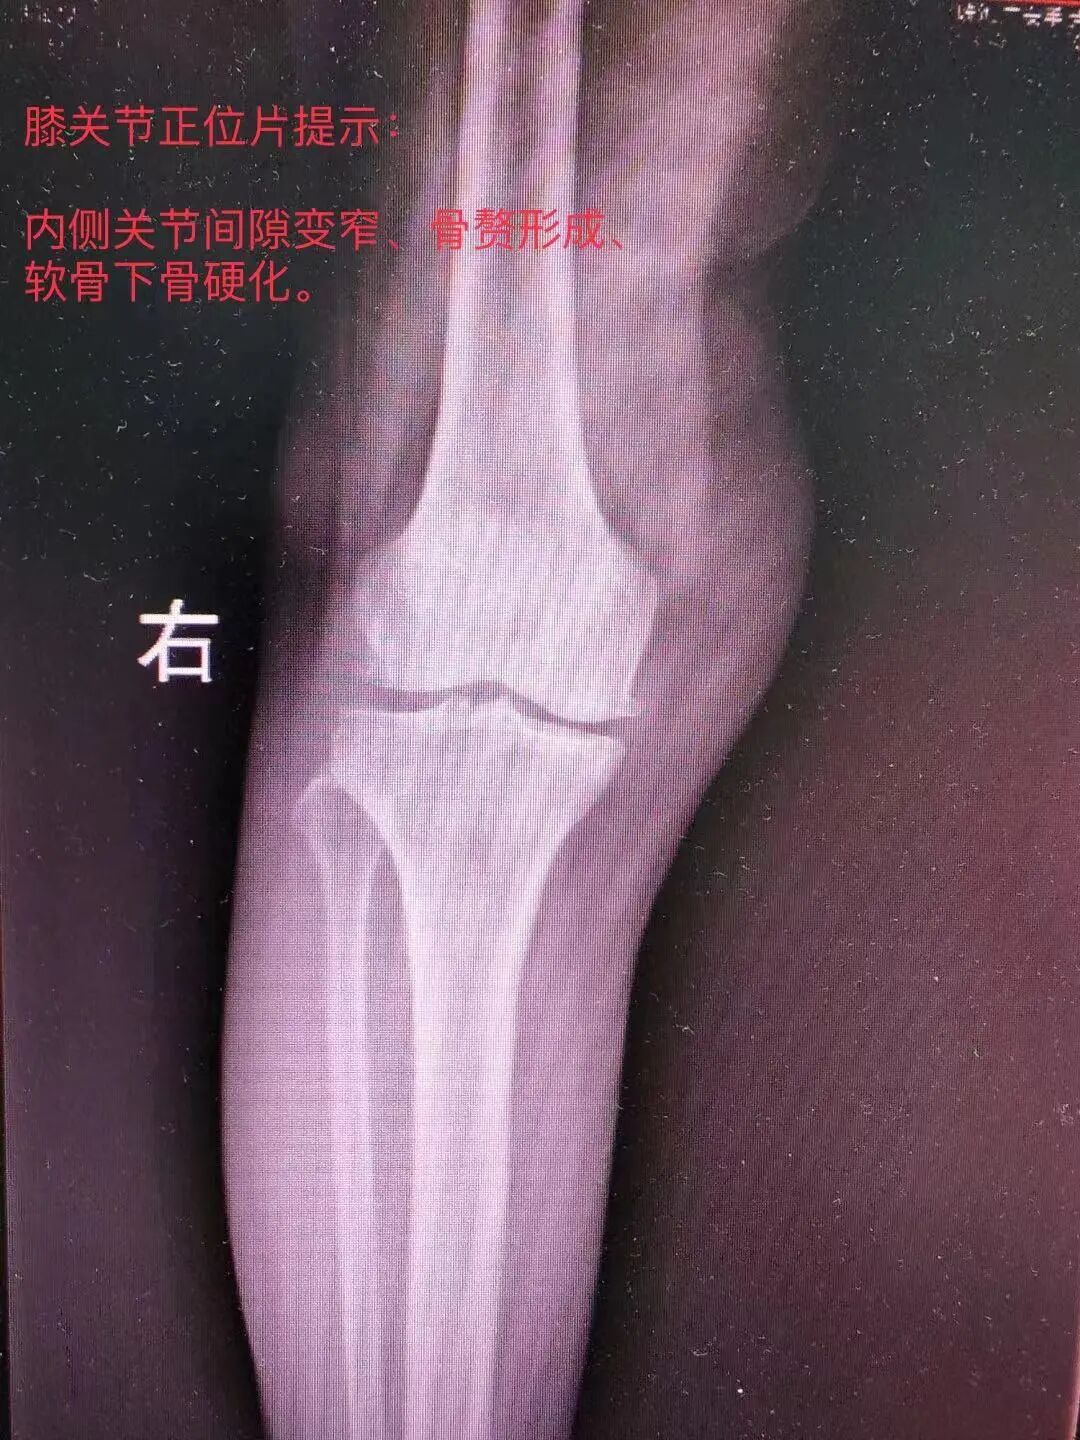

家人紧急之下把吴女士带到就近医院看诊,在注射玻璃酸钠,口服营养软骨药物治疗后,症状无明显改善。为求进一步专科治疗,2022年10月27日转来我院继续治疗。

关节科主任邓群波了解到:吴女士一年前已经出现了这个右膝关节疼痛,尤其是跳广场舞或者下蹲做家务后,疼痛会加重。但她瞒着家人,自己到药店购买了止痛药物,最近这两个月止痛药物已经没有什么效果了,走路都受到了影响。于是安排了患者住院进行进一步详细检查。

结合患者病史、查体及影像学资料,经科内会诊后决定给吴女士行人工单髁关节置换术,术中所见: